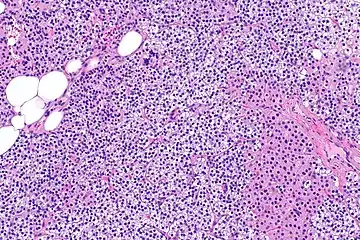

Parathyroid hyperplasia low mag.

Parathyroid hyperplasia medium mag.

Parathyroid hyperplasia high mag.

Primary hyperplasia of the parathyroid gland, results from both hypocalcaemia and increased phosphate levels by decreasing expression of calcium sensing receptors and vitamin D receptors at the parathyroid gland.[8][4] These decreases in receptor expression lead to hyperfunctioning of the parathyroid. Hyperfunction of the parathyroid gland is thought to exacerbate primary hyperplasia which evolves further to a secondary more aggressive hyperplasia. Histologically, these hyperplasic glands can be either diffuse or nodular.[24] Primary hyperplasia, usually resulting in diffuse polyclonal growth is manly related to reversible secondary hyperparathyroidism. Secondary hyperplasia of the parathyroid gland is more often a nodular, monoclonal growth that sustains secondary hyperparathyroidism and is the catalyst in the progression to tertiary hyperparathyroidism. Nodular hyperplastic glands in tertiary hyperparathyroidism are distinctly larger in both absolute size and weight up to 20-40-fold increases have been reported.[25][26][24]

Parathyroid glands are normally composed of chief cells, adipocytes and scattered oxyphil cells.[27][14] Chief cells are thought to be responsible for the production, storage and secretion of parathyroid hormone. These cells appear light and dark with a prominent Golgi body and endoplasmic reticulum. In electron micrographs, secretory vesicles can be seen in and around the Golgi and at the cell membrane. These cells also contain prominent cytoplasmic adipose.[27][14] Upon onset of hyperplasia these cells are described as having a nodular pattern with enlargement of protein synthesis machinery such as the endoplasmic reticulum and Golgi. Increased secretory vesicles are seen and decreased intercellular fat is characteristic.[27][24] Oxyphil cells also appear hyperplasic however, these cells are much less prominent.